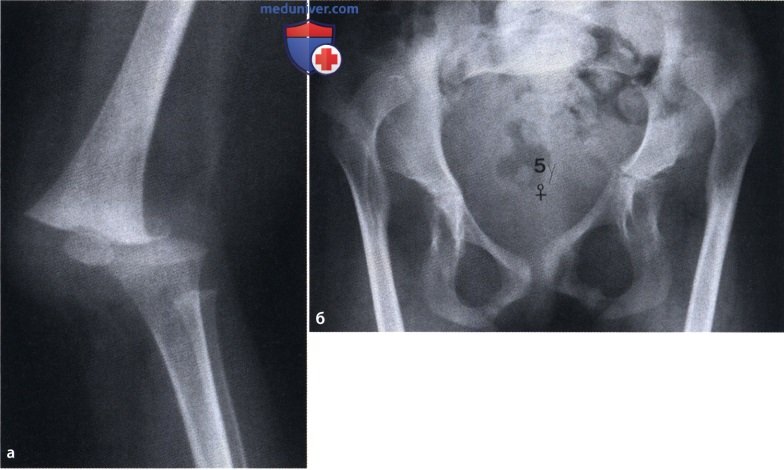

Ларсена йохансона

Ларсена йохансона 146 фото